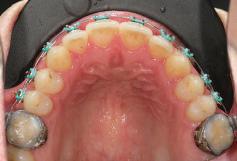

орални снимки и снимки на позата, пал пация на мускулите, брукс-чекър, оклу зограми, кондилография, рентгеногра фии, СВСТ и ядрено-магнитен резонанс на темпоромандибуларните стави). Преди началото на ортодонтското лечение всички стари възстановява ния бяха свалени и бяха заменени с дъл госрочни временни от хибридна керами ка. На девитализираните зъби бе прове дено ендодонтско релечение. Индивиду ализиран оклузален сплинт бе направен с цел да се постигне контролирано репо зициониране на долната челюст, като носенето му продължи три месеца до възстановяване на правилната позиция на ставния диск и затихване на орофаци алната болка и дискомфорт в ставата. Брекетите в горната челюст бяха за лепени, за да започне подреждането и нивелирането на зъбите, докато паци ентът все още носеше сплинта. След края на терапията със сплинта бе на правена кондилография, за да се потвър ди триизмерната позиция на долната челюст. След залепване на брекетите в долна

та челюст 4 минивинта (TADs) бяха по ставени в максилата – 2 в небцето и 2 интрарадикуларно във фронта, с цел да се извърши интрузия на цялата зъбна дъга, да се коригира гингивалната усмивка и да се позволи провеждането на обратна на часовниковата стрелка авторо

Цели на лечението и лечебен план Целите на лечението бяха следните: нивелиране и подреждане на зъбите и в двете зъбни дъги; отваряне на пространство за липсващия латерален резец; коригиране на отношенията при канините и моларите до клас I; и корекция на отклонението на срединната линия. Лечебният план включваше: корекция на отношенията при кучешките зъби и мола рите до клас I с дистализира не на максилата; отваряне на пространство в областта на #22 за поставя не на единичен имплант; корекция на срединната ли ния; и създаване на място за раз ширяване на зъб #12 и апрок симална редукция в долната челюст с цел подобряване на несъответствието по Болтън и осигуряване на подобра оклузия. Изпълнение на лечебния план Този случай бе изпълнен със системата за алайнери Invisalign (Align Technology). Одобреният първоначален лечебен план предвиждаше 49 алайне ра с дистализиране на задни те горни зъби до клас I (прибли зително с около 3.5 мм; фиг. 5). За бъдещия имплант в областта на липсващия латерал бе планирано пространство от 6.5 мм, докато във фронталния сегмент на долната челюст бе предвидена апроксимална редук ция. В дясната страна бутон за ластици клас II бе поставен на зъб #47 вместо на зъб #46, за да не се увреди короната на импланта. Понеже пациентката жи вееше в чужбина,

Dental Tribune Bulgarian Edition / октомври 2022 г.18 воначалния план. Тези пробле ми бяха адресирани чрез допъл нителна поръчка на алайнери с торк контрол и зададено екст рудиране на задните зъби с цел установяване на добри оклузал ни контакти в дисталните об ласти, като бяха предвидени и оптимизирани атачмънти с контрол над корените за корекция на ангулацията на макси ларните резци (фиг. 8). Резултати от лечението Панорамната рентгено графия след ортодонтското лечение показа благоприятна паралелна позиция на съседни те зъби, подходяща за поставя не на имплант в областта на #22, както и конвергенция на ко рените на зъби #44 и 45 (фиг. 9), но преценихме, че няма да от деляме допълнително лечебно време за коригирането ѝ поради факта, че пациентката бе мно го доволна от постигнатия до момента резултат. След при ключване на лечението бяха постигнати отлични взаимо отношения клас I при мола рите и канините, а срединни

съвпадаха. Върху им